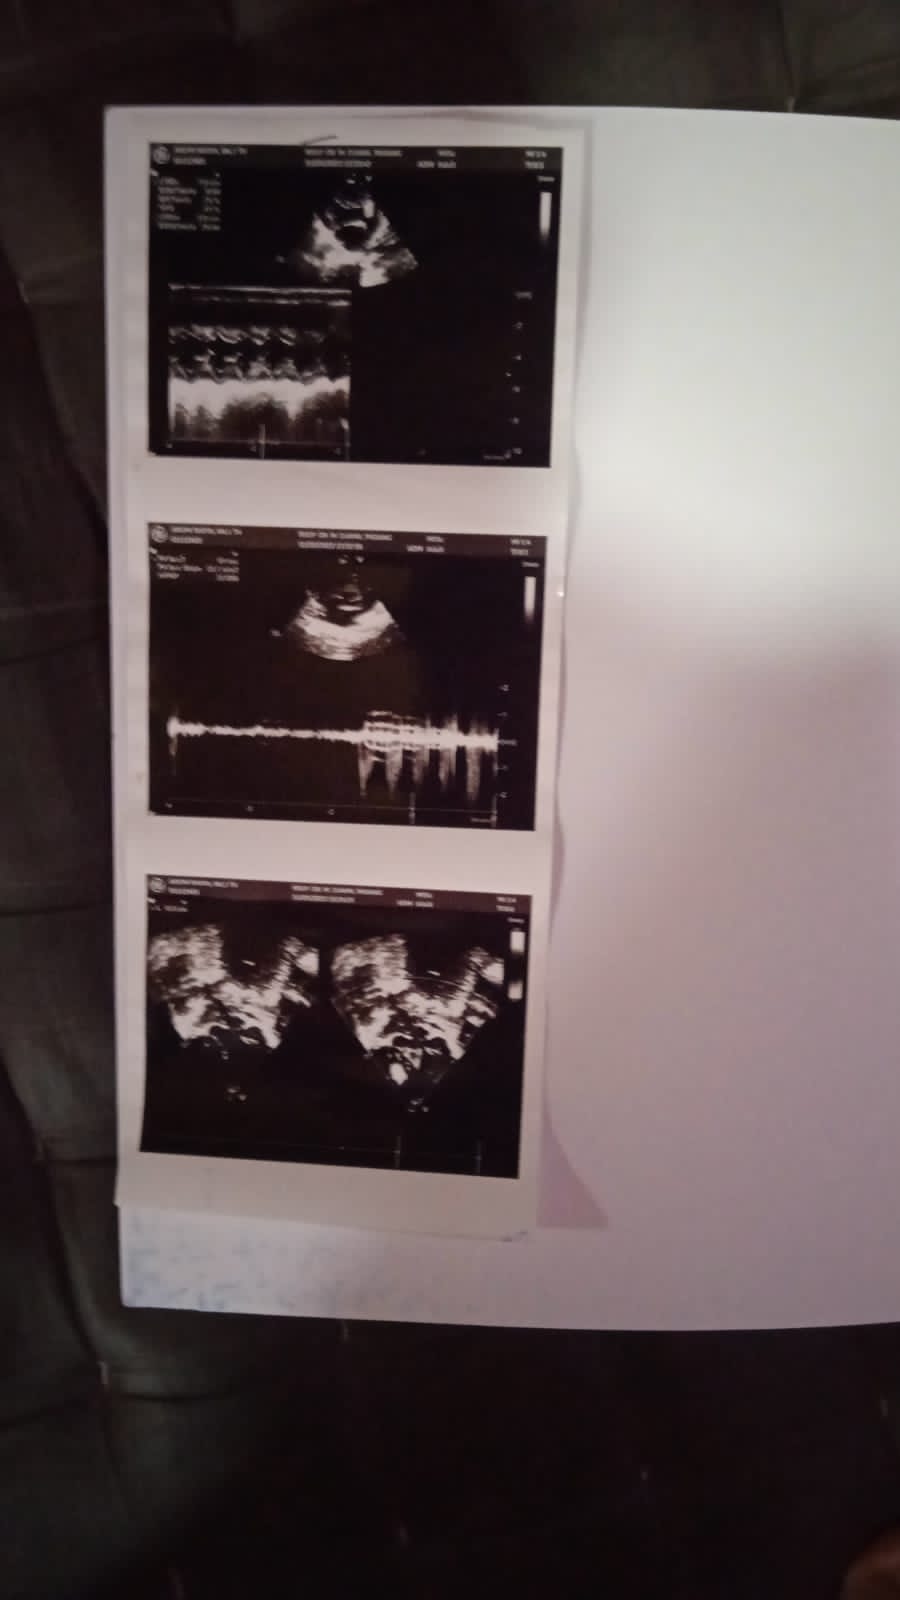

Anakku masih rutin menjalani kontrol ke rumah sakit sebulan sekali dan echo-nya masih berjalan 6 bulan sekali.

Aku ibunya Arumi mau mengabarkan kondisi anakku saat ini. Walaupun sekarang kondisinya baik, tapi hasil echo kemarin belum ada perkembangannya.

Sejauh ini dokter mengatakan masih aman dan dokter menyarankan agar berat badan anakku harus ditingkatkan, karena berat badannya tidak naik-naik. Dokter menyarankan asupan gizinya ditingkatkan.